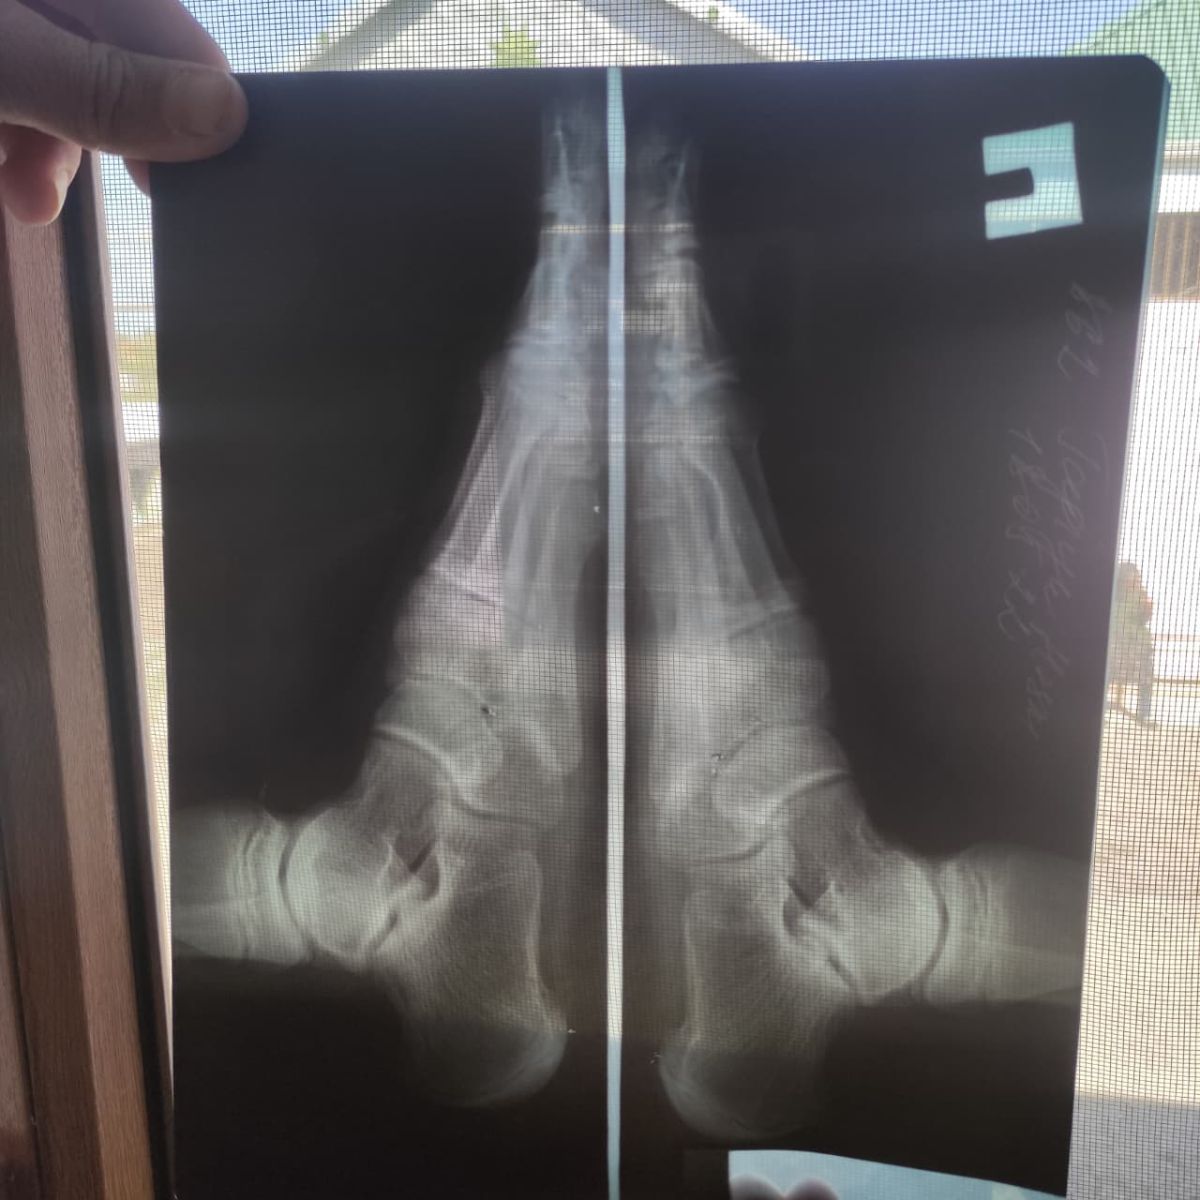

Uşağın ayağındakı problem artıq üzə verib. Ayağının biri digərindən gödəkdir. Ayağının altı isə düzdür. Belə adamı necə əsgər apara bilərlər? Əgər aparırlarsa, bəs onda niyə Akedemiyaya girişinə icazə vermədilər.

Samux rayon sakini 2007-ci il təvəllüdlü Tağıyev Həsən Ağalar oğlunun 01.08.2025-ci il tarixdə Dövlət Tibbi-Sosial Ekspertiza və Reabilitasiya Agentliyində yekun tibbi müayinəsi aparılıb.

Müayinə zamanı vətəndaşın Forma-44 göndərişində qeyd edilən diaqnoz öz təsdiqini tapmayıb.

Bu səbəbdən də qanunvericiliyə uyğun olaraq 21.08.2025-ci il tarixdə hərbi xidmətə yararlı olması barədə qərar qəbul edilib.